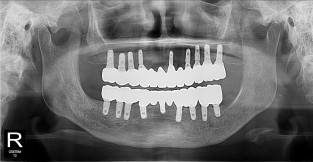

• 10

풀케이스

치료기간 : 2022-03-18 ~ 2023-09-15

1. 상기 x-ray 이미지 모두 동일한 해당 의료기관에서 진료한 환자입니다.

2. 상기 x-ray 이미지 모두 동일 인물의 것입니다.

3. 치료 전 이미지는 2022-03-18에 촬영했으며, 치료 후 이미지는 2023-09-15에 촬영하였습니다.

4. 상기 x-ray 이미지 모두 동일 조건에서 환자분의 동의를 받아촬영되었습니다.

* 임플란트 시술은 환자분의 상태(고혈압, 당뇨 등)에 따라 부작용이 있을 수 있으니, 반드시 전문의와 상담이 필요합니다.

* 임플란트 수술 부작용

: 수술 후 출혈, 교합, 통증, 붓기, 염증 등의 문제점이 발생할 수 있습니다.)